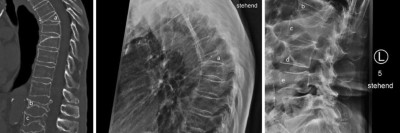

Patient mit chronisch progredienten Knochenschmerzen – Ihre Diagnose?

Berichtet wird der Fall eines 82-jährigen Mannes mit Knochenschmerzen, die im Laufe von fünf bis sechs Jahren kontinuierlich zunahmen. Es bestand eine Osteomalazie bei Hypophosphatämie. Die Ursache für diesen Befund fand sich aber erst in der erweiterten Diagnostik.

Indikationen zur konventionellen Bildgebung am Ellenbogen/© Rentschler V et al. / all rights reserved Springer Medizin Verlag GmbH, Transrektale MRT/© Springer Medizin, Osteoporotisch bedingte Sinterungsfrakturen der Wirbelsäule/© L. Heuchemer, D. Emmert, T. Bender et al./Springer Medizin Verlag GmbH, Person isst eine Krankenhaus-Mahlzeit/© gballgiggs / Stock.adobe.com (Symbolbild mit Fotomodell), Springer Medizin Podcast - Stürze im Alter/© Gatz M et al / all rights reserved Springer Medizin Verlag, Mann erhält einen CT-Scan /© Mark Kostich / stock.adobe.com (Symbolbild mit Fotomodell), Person hält zwei Tabletten in der Hand/© AsiaVision / Getty Images / iStock (Symbolbild mit Fotomodell), Fallbeispiel Röntgenaufnahme des Thorax in zwei Ebenen/© Reinke L. et al. / all rights reserved Springer Medizin Verlag GmbH, Frau bei Knochenmineraldichte-Messung/© gelmold / stock.adobe.com (Symbolbild mit Fotomodell), Senior im Krankenhausbett mit gebrochenem Fuß/© Mat Hayward / Stock.adobe.com (Symbolbild mit Fotomodell), Abb - Röntgenaufnahme der linken Hüfte anterior-posterior/© K. M. Peters, Ekzem an der Brustwarze/© T. Jansen, Auch der Knochen leidet bei Diabetes - oft schon im mittleren Lebensalter/© Trueffelpix / stock.adobe.com, Ultraschalllängsschnitt der Fossa olecrani/© Springer Medizin Verlag GmbH, Search Icon, Kind streckt sich freudig, Mutter sitzt und lacht/© BioMarin